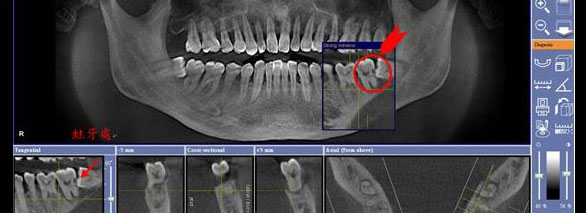

CBCT锥形束CT

360度旋转扫描即得患者骨量信息、软组织信息、咬合关系等头部完整数据,重组三维立体图像,超高清低辐射,医生可从任意角度观察分析病例。

数字化种植牙方案设计

整合患者口内的CBCT数据及咬合关系,将完整数据上传到会诊系统中,与数据库内数万病例进行综合对比、分析,规避术中并发症,模拟手术过程及预测术后治疗效果,以数字化全息影像为基础的方案设计对于患者来说更形象、更易懂,患者参与度更强。